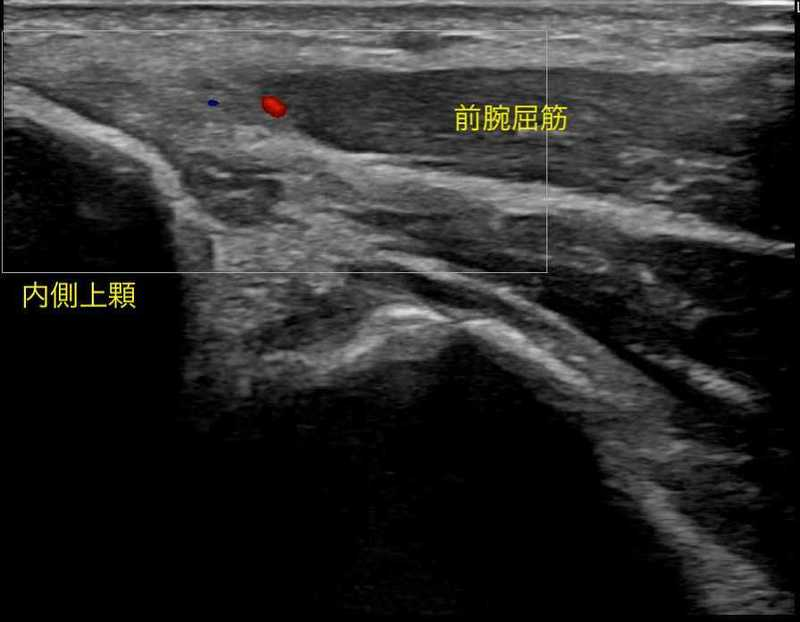

内側上顆炎(別名:ゴルフ肘・テニス肘 内側型)

内側上顆炎は外側上顆炎と同様に肘の内側に付いている筋肉に過剰な負荷がかかり過ぎると腱に痛みが出現します。

日常生活では、手首を手のひらの方向に向けるような動き(掌屈動作)や引っ張るような動きで痛みが出ます。

スポーツ動作では、テニスのフォアハンドで打つときなどで痛みが出現する可能性があります。

この痛みを我慢し続けると、肘の内側いある腱が変性を起こし、痛みが持続してしまいます。

症例提示

【年齢】50歳 【性別】男性

2021年6月ごろ テニス時に肘関節内側部に疼痛出現。

特にテニスの練習(フォアハンド・サーブ)中〜練習後に疼痛を認めた。

以前から手関節、肘関節、肩関節に疼痛を認めることはあったが

今回疼痛が強いため2021年12月受診。リハビリと併用して拡散型衝撃波を実施。

下に治療中の疼痛推移を示します。

体外衝撃波は2回施行し、漸減的に疼痛が軽減していきました。

テニスにも復帰でき、通院終了となりました。